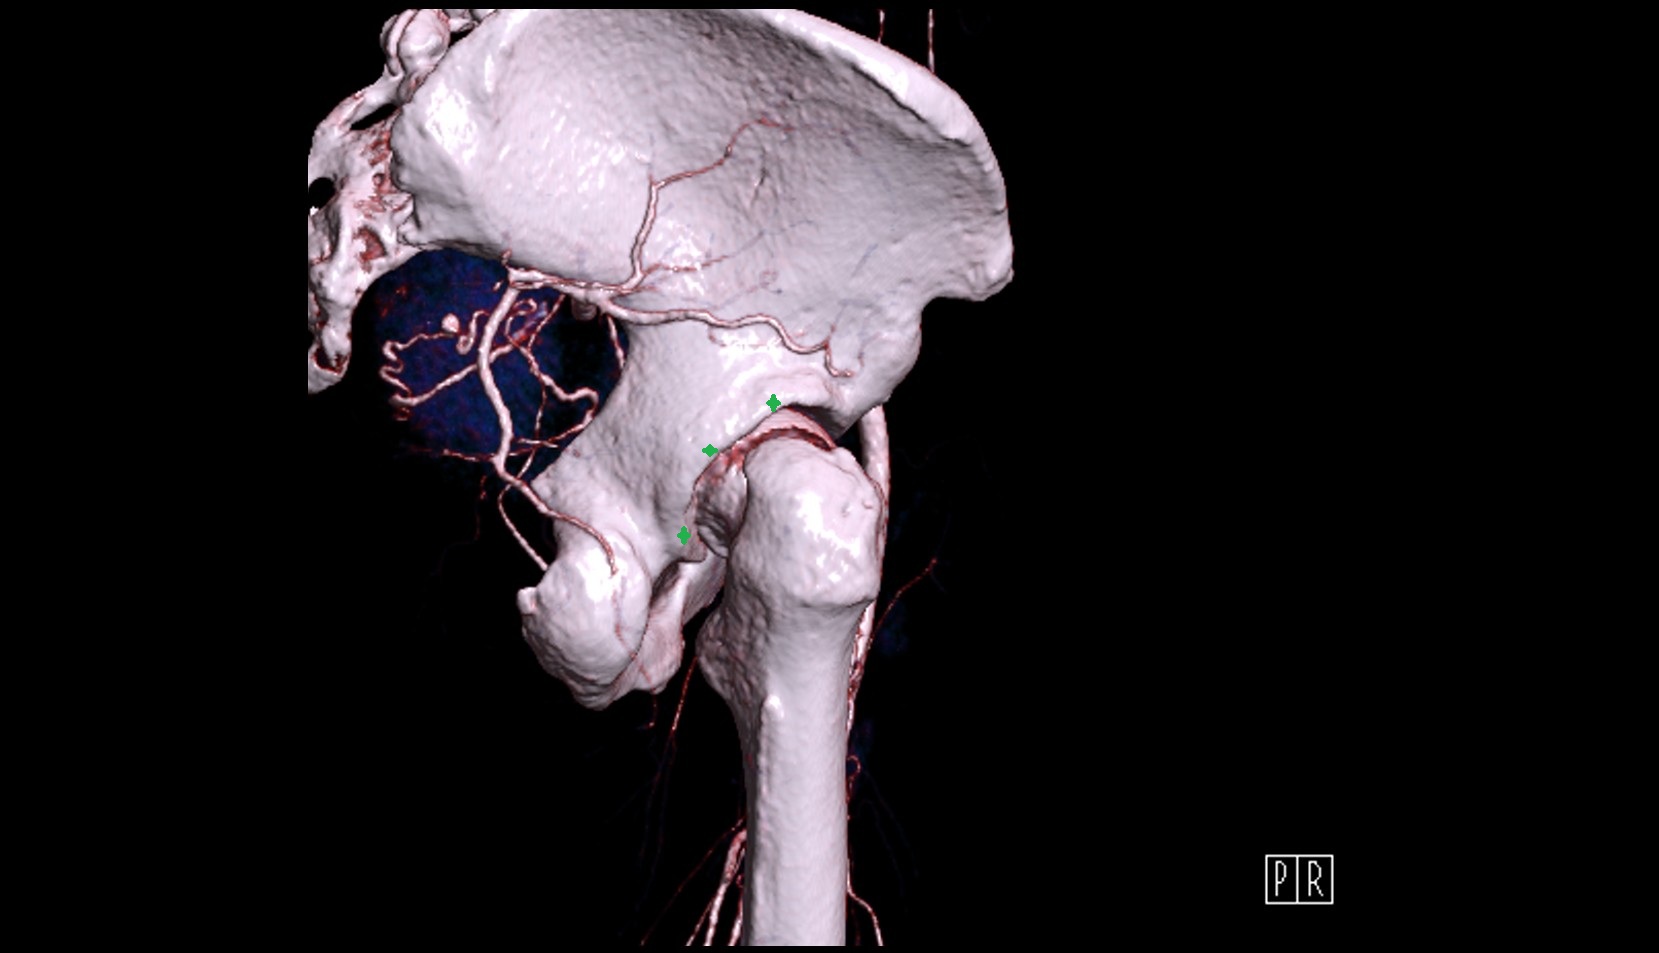

- External iliac artery

- Femoral artery

- Internal iliac artery

- Medial circumflex femoral artery

- Obturator artery

- Superior gluteal artery